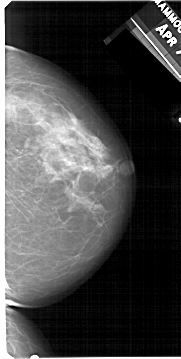

A_1512_1.LEFT_CC

LEFT_CC LINES 5341 PIXELS_PER_LINE 2716 BITS_PER_PIXEL 12 RESOLUTION 43.5 OVERLAY